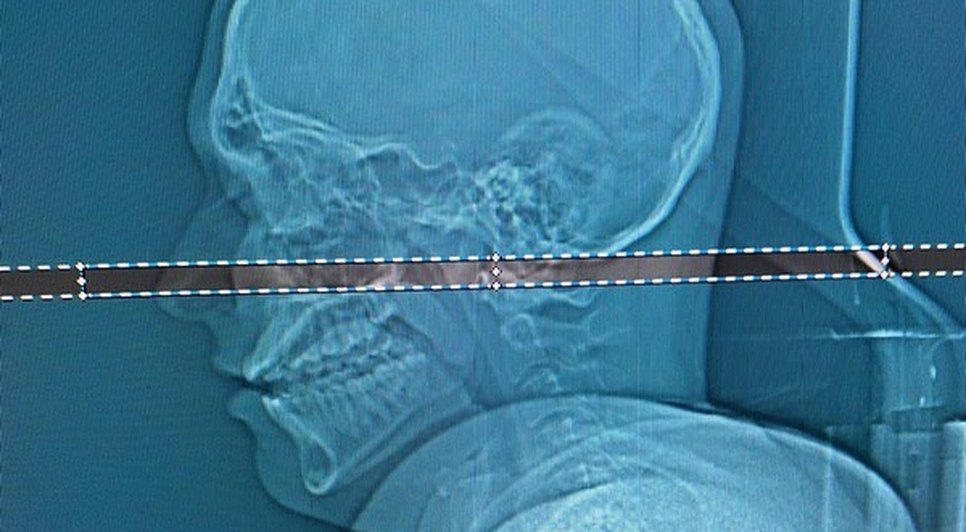

Um estudante de 21 anos, identificado como Mateus Facio, descobriu que estava com uma bala alojada na cabeça quatro dias depois de achar que havia sido atingido por uma pedra. O ferimento ocorreu durante as comemorações de Ano-Novo em Cabo Frio, no Rio de Janeiro.

O jovem, que é de Juiz de Fora(MG), viajou para o Rio com amigos e aproveitou as festividades sem sentir dores, até que no dia 04 de janeiro ele acordou com dificuldades de mexer o braço direito. A bala foi revelada em um exame de tomografia e foi retirada mediante uma cirurgia, que durou cerca de duas horas e foi realizada em Minas.

"Foi arriscado, bem arriscado para o paciente. A gente acredita que em 20, 30 dias, ele vai seguir a vida normal dele", explicou o neurocirurgião responsável pelo procedimento. A bala ficou em um local muito perigoso e, se estivesse em milímetros de diferença, poderia ter causado até a paralisação de metade do corpo do jovem.